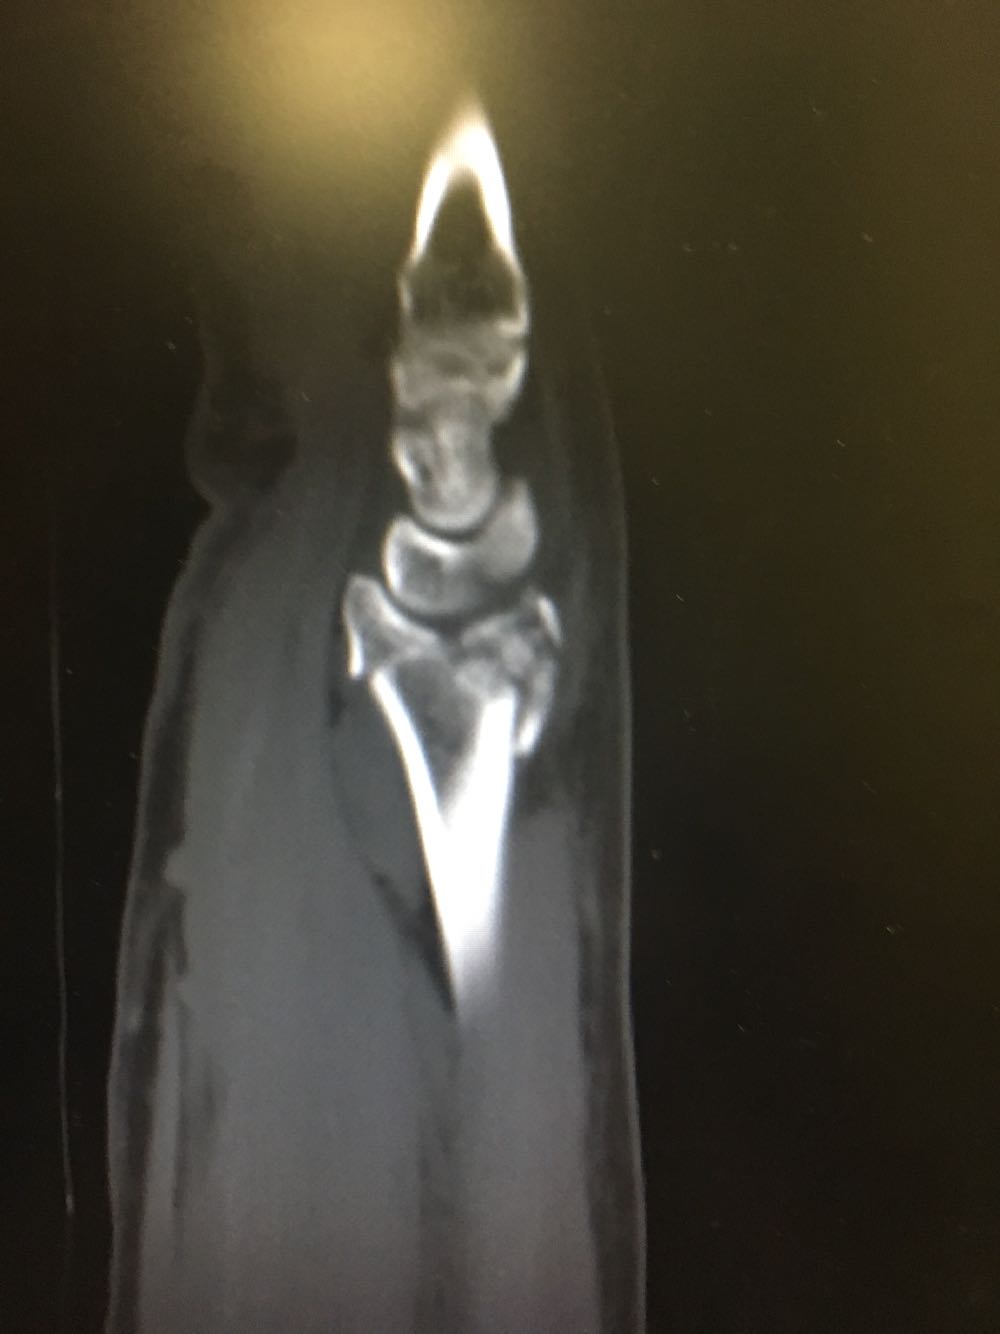

右尺桡骨双骨折

患者,男性,52岁 主诉:摔倒后右腕关节活动受限2天 现病史:患者于2天前于不慎,身体向右摔倒,右手掌着地后突感右侧腕部剧烈疼痛,后出现肿胀伴活动障碍,否认头晕头痛、恶心呕吐等不适,未见淤斑淤点,遂至我院就诊,查X片示:右侧桡骨远端及齿骨茎突骨折,现为进一步诊治收治入院,发病以来,神清,精神可,胃纳夜眠可,二便无殊,体重无明显变化。

查体:右手腕部压痛明显,伴活动受限,其余部位压痛不明显,患侧手指感觉及运动正常。 辅检:腕部CT

诊断:尺桡骨远端骨折(右侧) 治疗:完善术前检查后手术内固定